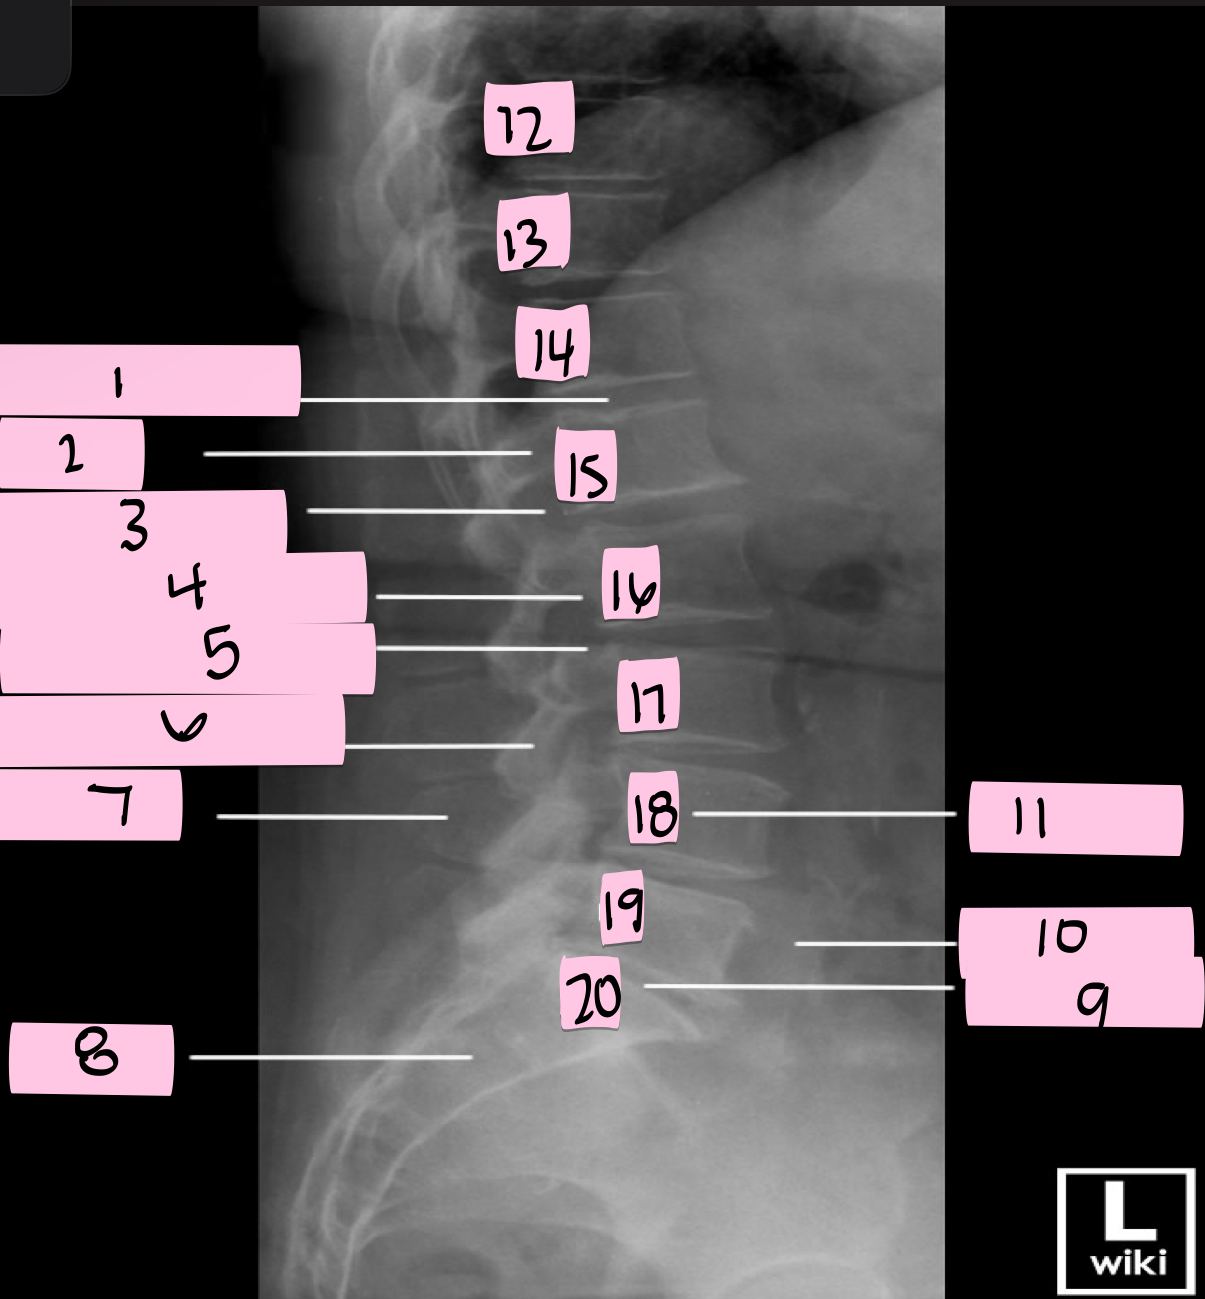

What is 1 pointing to?

Intervertebral disk

What is 2 pointing to?

Pedicle

What is 3 pointing to?

Intervertebral foramen

What is 4 pointing to?

Inferior vertebral notch

What is 5 pointing to?

Superior vertebral notch

What is 6 pointing to?

Inferior articular process

What is 7 pointing to?

Spinous process

What is 8 pointing to?

Sacrum

What is 9 pointing to?

L5 S1 joint

What is 10 pointing to?

Iliac crest

What is 11 pointing to?

Vertebral body (L4)

What is 12 pointing to?

T10

What is 13 pointing to?

T11

What is 14 pointing to?

T12

What is 15 pointing to?

L1

What is 16 pointing to?

L2

What is 17 pointing to?

L3

What is 18 pointing to?

L4

What is 19 pointing to?

L5

What is 20 pointing to?

S1